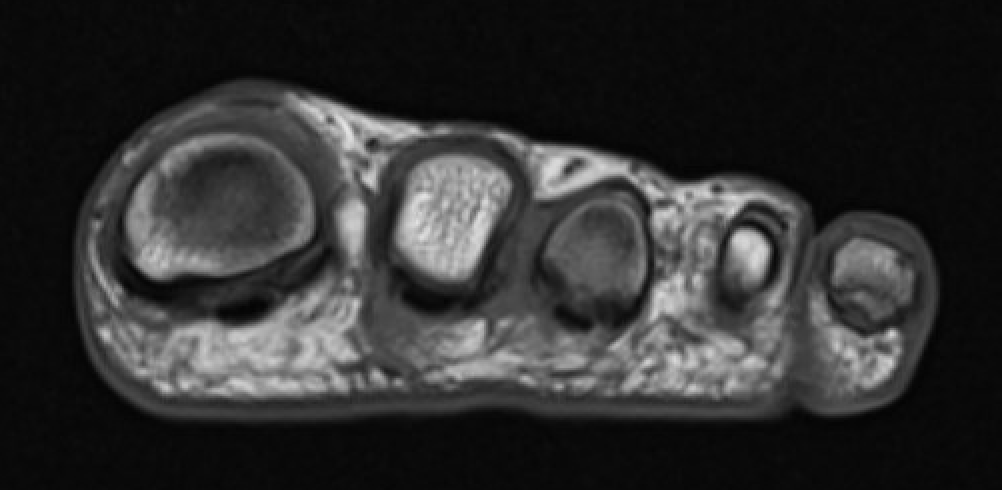

MRI

Obliteration of fat pad

Dumbbell shaped lesion between metatarsal heads

Mortonmorton

Morton's neuroma 3rd webspace

Mortonsmortons

Morton's neuroma 2nd webspace